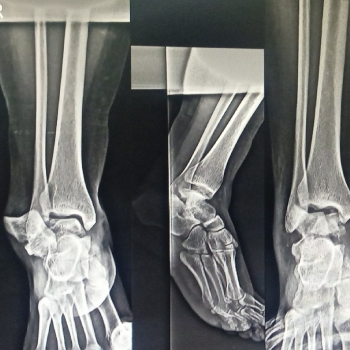

Lisfranc Injury Treatment

Lisfranc injury treatment includes immobilization, rest, pain management, and physiotherapy. Moderate to severe cases may require surgical fixation, followed by structured rehabilitation programs to restore stability, improve mobility, and ensure proper long term recovery.